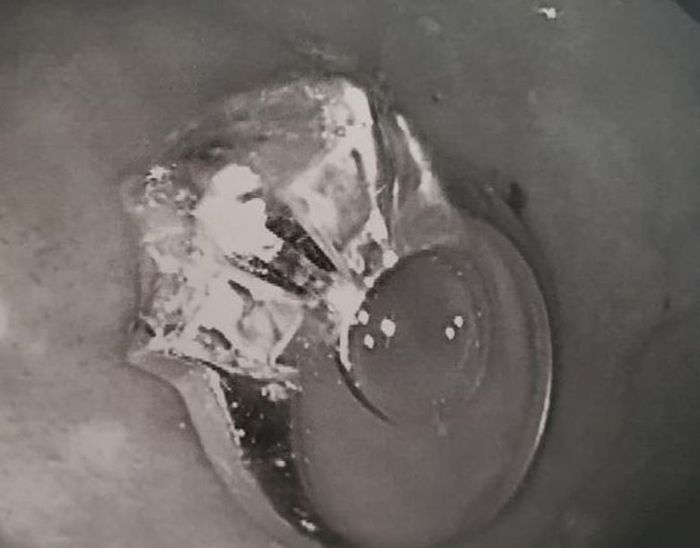

Melansir dari Mirror (15/9/2019), cincin itu akhirnya bisa diambil, tetapi setelah Jenna melewati cobaan yang berat.

Suaminya singat cerita membawa Jenna ke dokter di mana dia harus memberi tahu sekelompok dokter dan perawat bahwa dia menelan cincin pertunangannya.